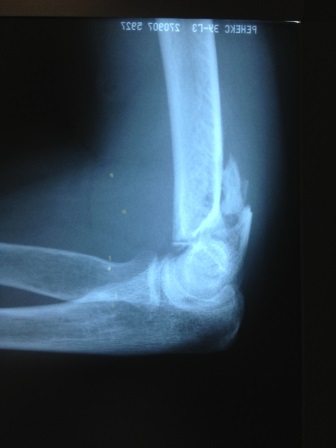

Рис.1. Пациентка, 52 года. Закрытый внутрисуставной оскольчатый перелом нижней трети правой плечевой кости со смещением костных отломков. Закрытый внутрисуставной перелом локтевого отростка правой локтевой кости со смещением костных отломков.